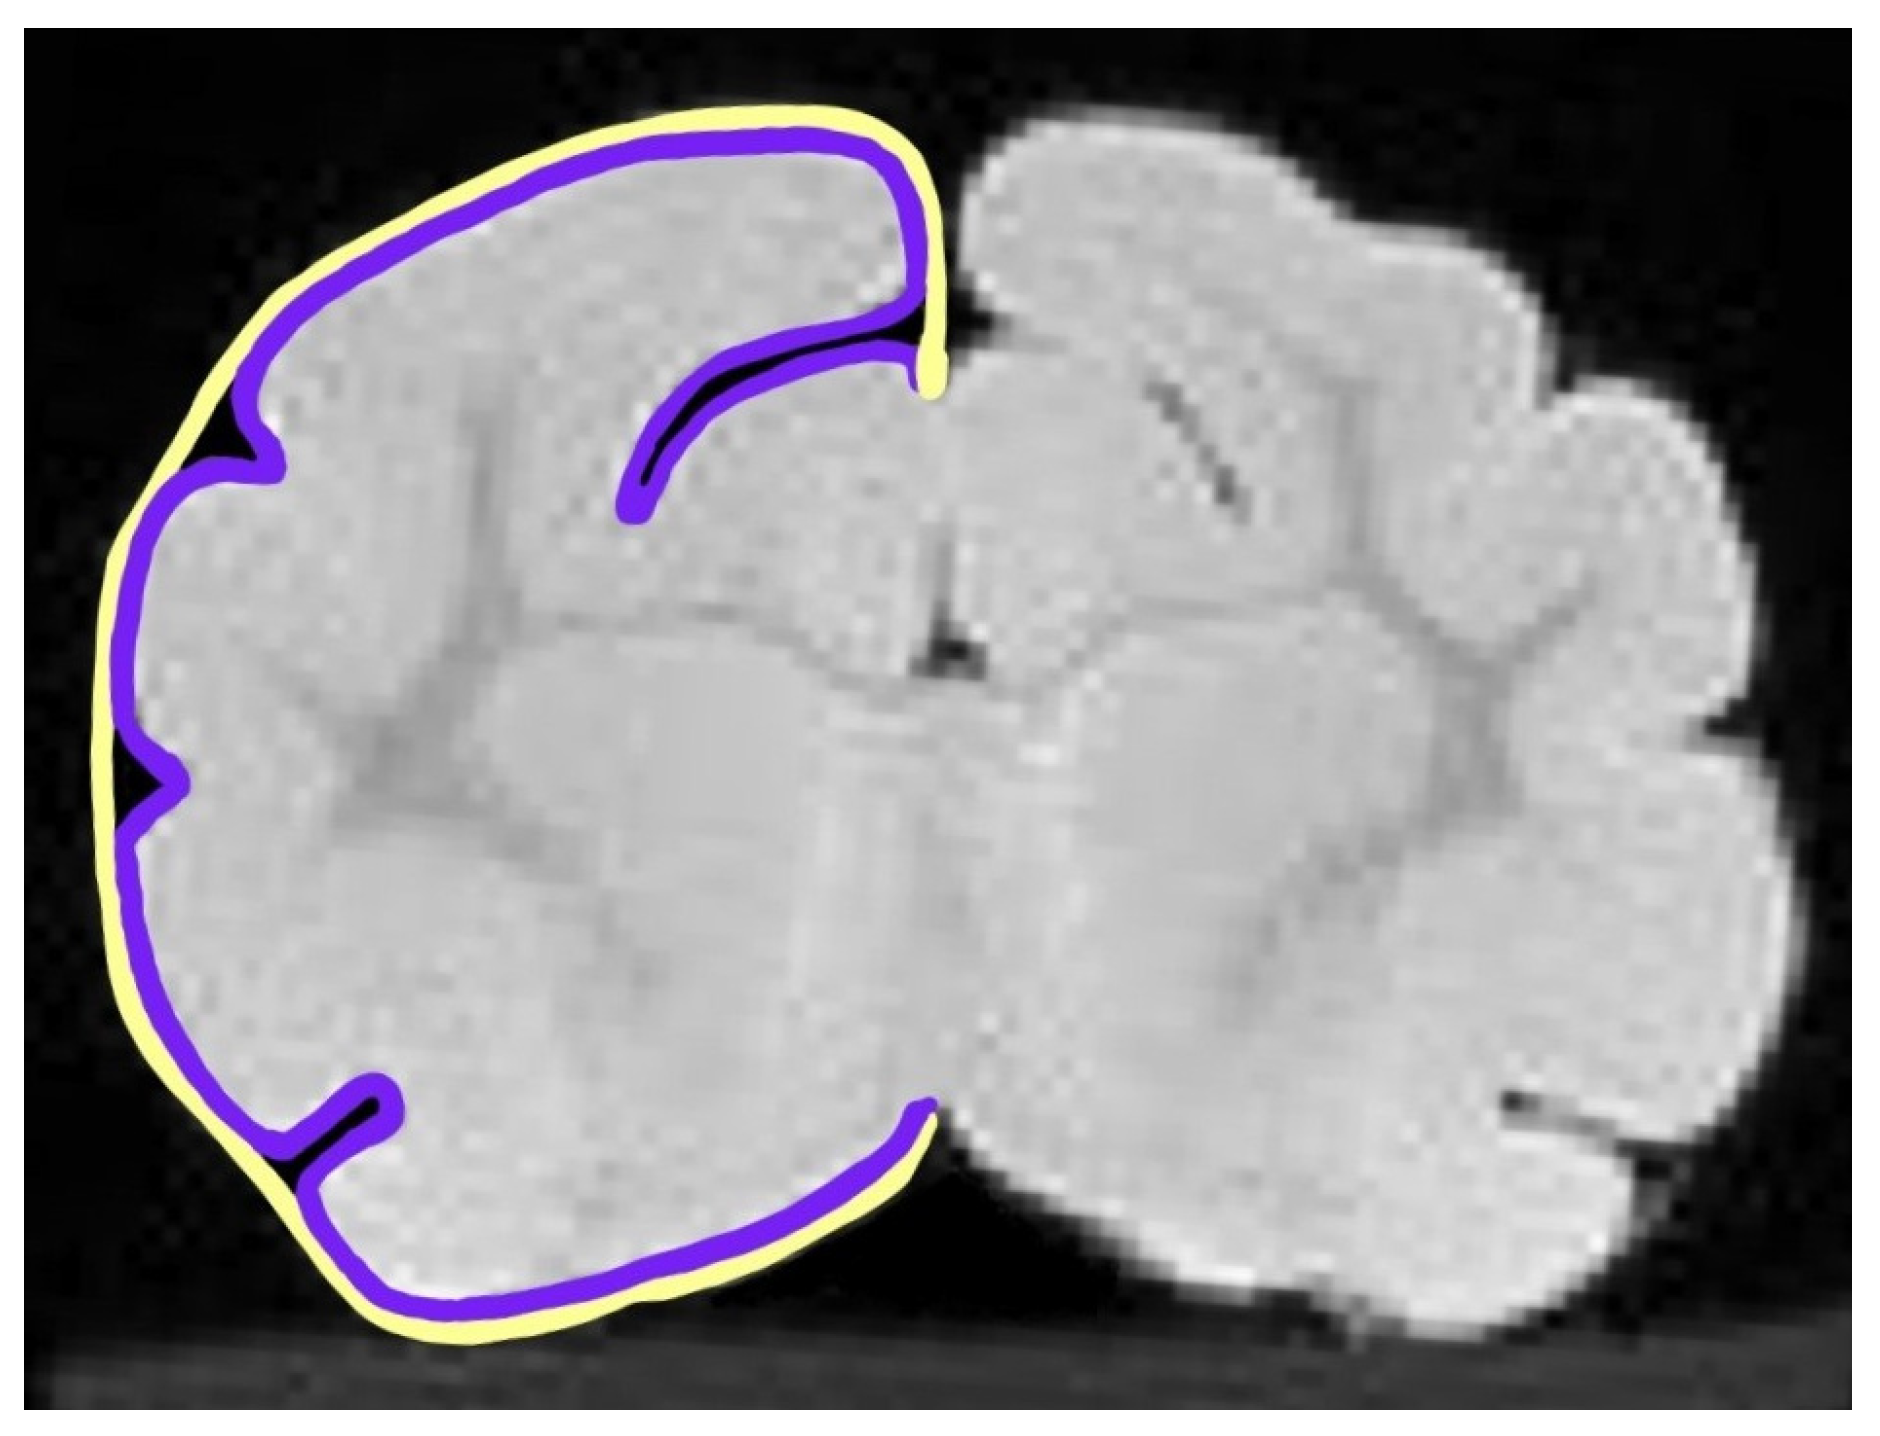

2.4. Gyrification Index